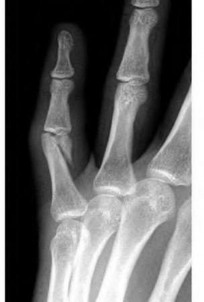

A 30-year-old male sustains a severe midfoot sprain. Radiographs reveal widening between the bases of the first and second metatarsals.

The primary ligamentous stabilizer disrupted in this classic Lisfranc injury connects which two osseous structures?

Explanation

The Lisfranc ligament is the strongest ligament in the tarsometatarsal joint complex. It courses obliquely from the lateral aspect of the medial cuneiform to the medial base of the second metatarsal. It acts as the primary stabilizer of the second metatarsal base. Disruption results in the classic widening between the first and second rays, often with an avulsion fragment ('fleck sign').